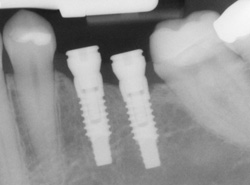

An excellent option for replacing missing teeth is a dental implant. The most common type of dental implant is the root-form implant which, as its name implies, is about the same size and shape as the root of a tooth. Root-form implants are made from titanium, and they are surgically placed in the jawbone where they heal firmly in place. After healing is complete, a crown or other dental restoration can be placed on the implant.

Implants can be used to support various dental restorations, including a single crown, a bridge, or a denture. Crowns and bridges are permanent restorations that are cemented to the implant and are not removable. Implant supported dentures are removable, but unlike traditional dentures, they snap on to the implants and remain firm and stable in the mouth.